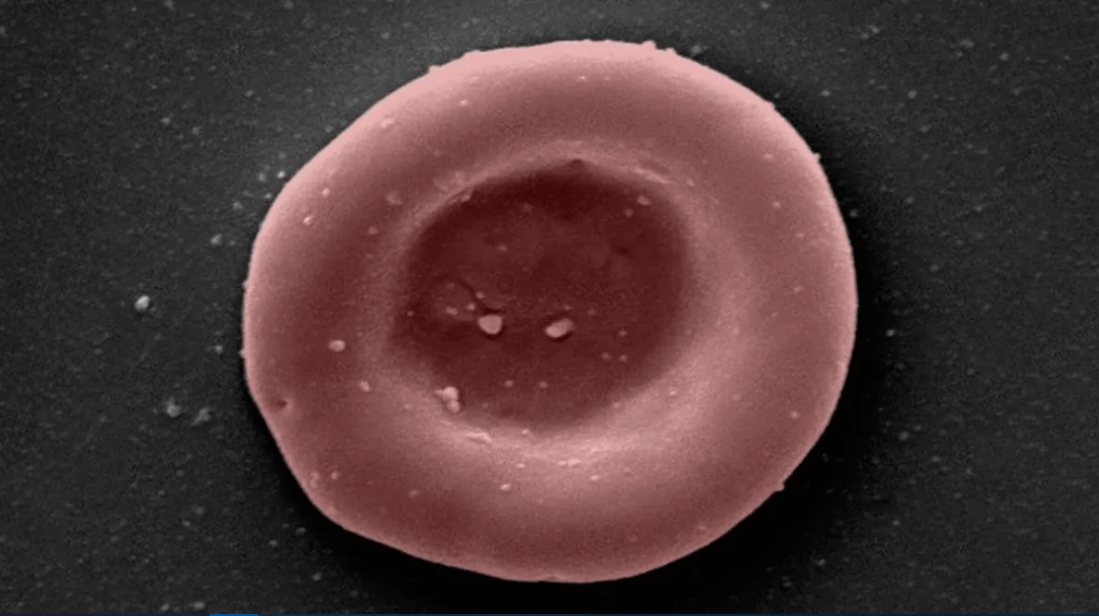

Пример микроскопического изображения молодого эритроцита, выращенного в лаборатории RESTORE.

Фото: NHSBT

Цель проекта — компенсировать нехватку редких групп крови. Из стволовых клеток человеческой крови биологи выращивают в лаборатории новые эритроциты. Недавно ученые совершили исторический прорыв, введя «новый» трансфузионный продукт в организм человека.